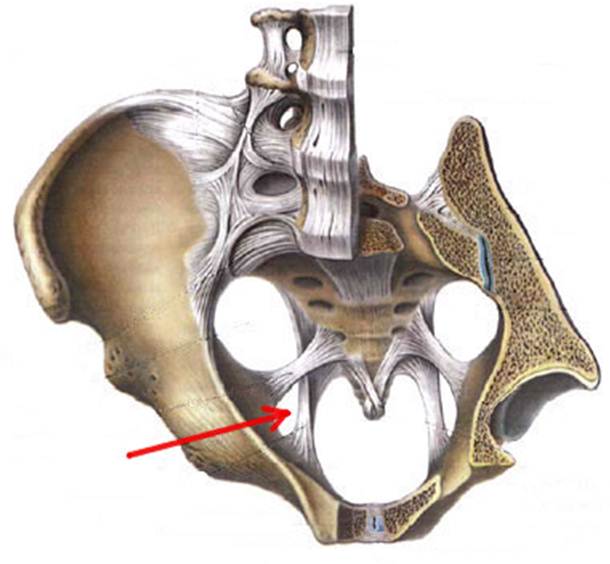

S: Стрелка указывает на lig. Sacrospinale

S: Стрелка указывает на лобковый симфиз (русский язык).

S: Стрелка указывает на foramen ishiadicum majus

S: Стрелка указывает на foramen ishiadicum minus

S: Стрелка указывает на membrana obturatoria (латинский язык).